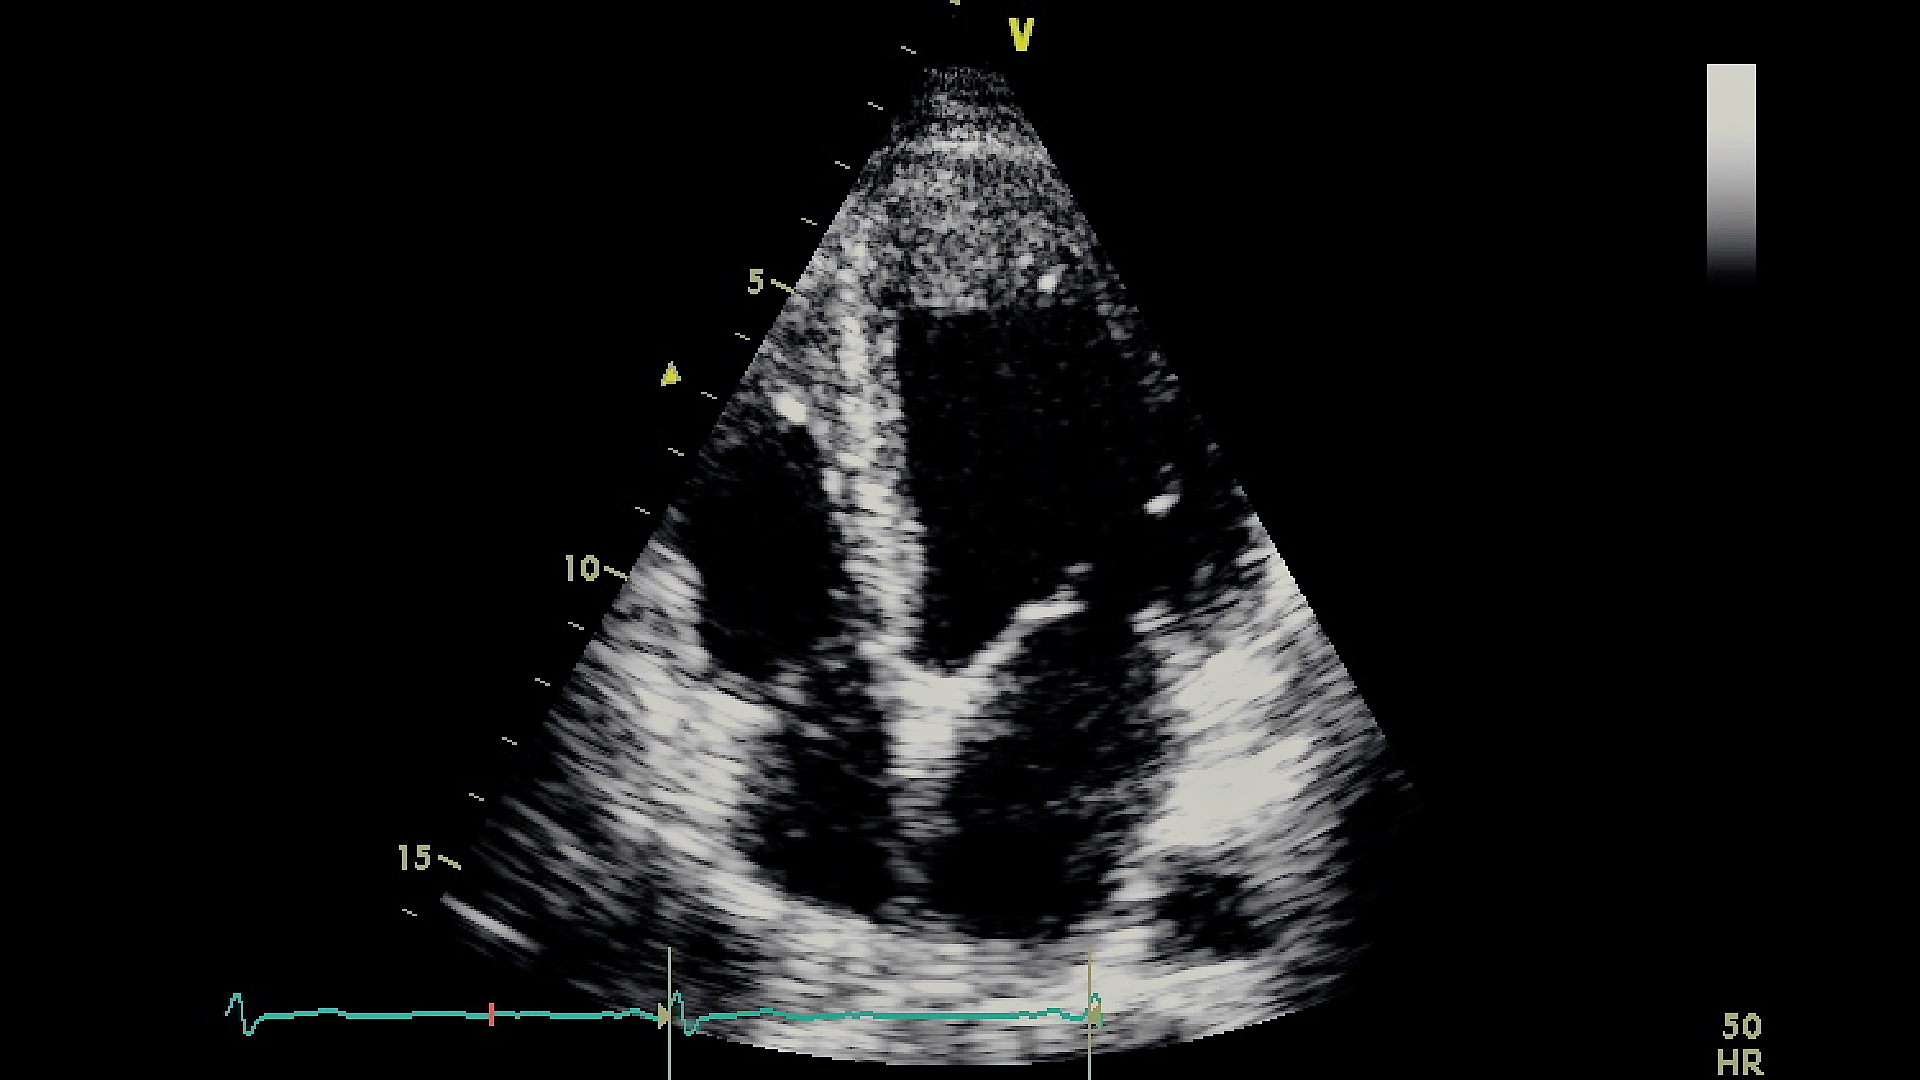

This work focuses on performing early MI detection by learning RWMA of the LV wall in the A4C view echocardiography. Figure 2 shows a captured frame representing the A4C view, which consists of four distinct heart chambers, numbered from 1 to 4, where 1 identifies the LV, 2 to 4 identifies the Right Ventricle, the Left Atrium, and the Right Atrium, respectively.

Refer to caption

Figure 2: Apical four-chamber view. The numbers from 1 to 4 marking the four different chambers correspond respectively to the LV, the right ventricle, the left atrium, and the right atrium